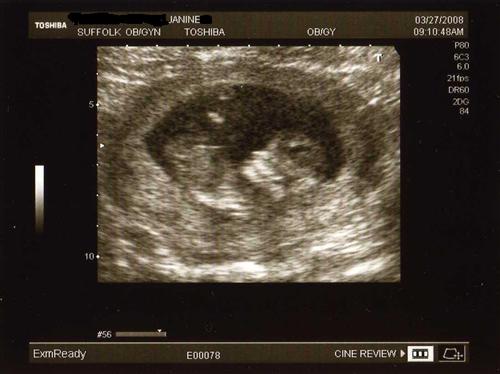

I wanted to share my 12 week sono pics that I had yesterday. Our little one was quite active, as I had a sugery cereal in the morning. Baby was rolling and waving, showing us all five fingers and was rubbing his/her eyes like it just woke up. They said baby looks good and healthy so far.

Good profile pic kicking